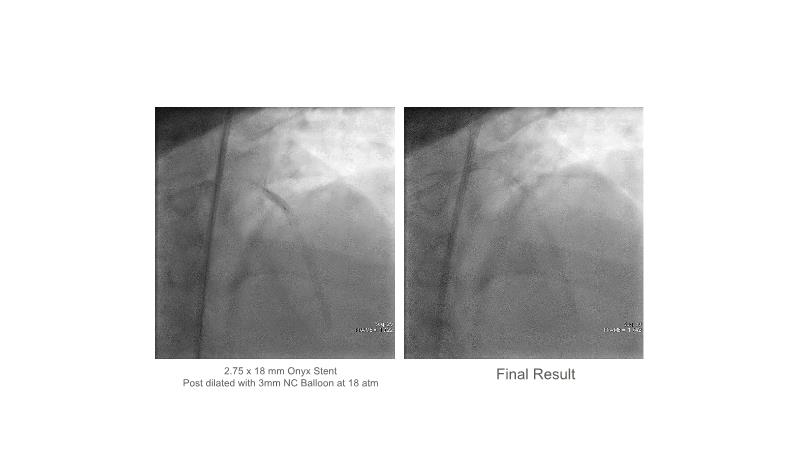

Over the last five years, we have learned that there is a new tool for treating calcium, the greatest enemy of interventional cardiology, which can take various forms: intravascular lithotripsy. In this session, look at how to master this technique in different scenarios, from eccentric calcified lesions to left main bifurcations.

- To understand the mechanism of action of intravascular lithotripsy (IVL) for the treatment of calcified lesions

- To learn how to safely utilise IVL in left main bifurcations